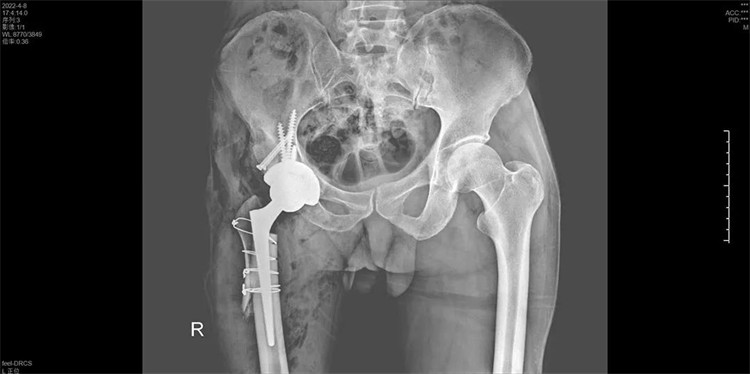

手術(shù)過程一氣呵成,手術(shù)歷時2個小時,出血200ML,順利地為周大伯進(jìn)行了右側(cè)人工全髖關(guān)節(jié)置換術(shù),將人工髖關(guān)節(jié)準(zhǔn)確地安裝在周大伯的真臼內(nèi)并做了牢固的固定。術(shù)后第1天周大伯就已下地行走。